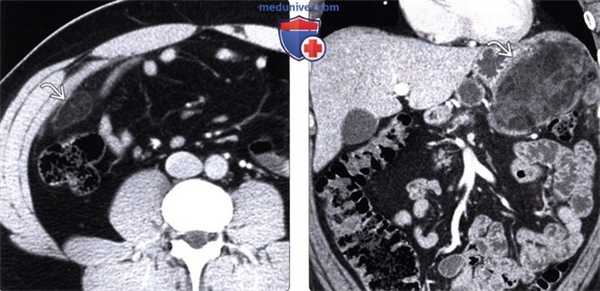

(Слева) На корональной КТ с контрастным усилением у пациента с болевой симптоматикой определяется инкапсулированное, содержащее жир объемное образование в правом нижнем квадранте сальника с помутнением окружающей жировой клетчатки, что характерно для инфаркта.

(Справа) На аксиальной КТ с контрастом у пациента после экстренной дистальной панкреатэктомии выявлено большое объемное образование с четкими контурами в левом верхнем квадранте сальника. Обратите внимание на наличие включений с плотностью жира в структуре образования. Инфаркты сальника, как в этом случае, могут иметь весьма большие размеры и симулировать опухоль (липосаркома) или канцероматоз.

(Слева) На аксиальной КТ у пациента с узелковым полиартериитом и болью в животе определяется помутнение жировой клетчатки в передних отделах сальника, соотносящееся с локализацией боли. Это проявление инфаркта сальника, вероятно, обусловлено васкулитом.

(Справа) На аксиальной КТ с контрастным усилением у одиннадцатилетнего мальчика с жалобами на боли в правом нижнем квадранте (живота) визуализируется четко очерченное, овоидной формы, жировой плотности объемное образование в правом нижнем сегменте, с помутнением прилежащей жировой клетчатки. Лечащий врач склонялся к диагнозу аппендицита, при оперативном вмешательстве был обнаружен инфаркт сальника.